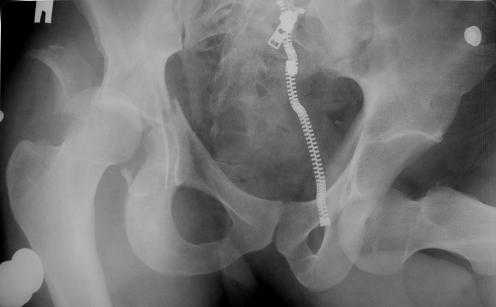

Уважаемые коллеги! Прошу посоветовать как лечить больного с двусторонним повреждением тазобедренных суставов. Пациент 30 лет поступил к нам в клинику по поводу закратого поперечного перелома свода, перелома задне -вехнего края правой вертлужной впадины, подвздошного вывиха правого бедра. Постравматического неврита правого седалищного нерва. Закрытого запирательного вывиха левого бедра. травма автодорожная 3 недели назад. Вправление вивихов при поступлении по месту жительства, получал скелетное вытяжение (слева в течении 2 недель).На контрольной Р-грамме обнаружена импрессия верхнего полюса головки левого бедра. Выполнено КТ.Планируем выполнить остеосинтез перелома правой ВВ наружным доступом.Подскажите пожалуйста, необходимо что либо предпринимать по поводу перелома головки левого бедра (в "Мюллере" описана костная пластика дефекта)? И как рано можно разрешить нагрузку на левую ногу.